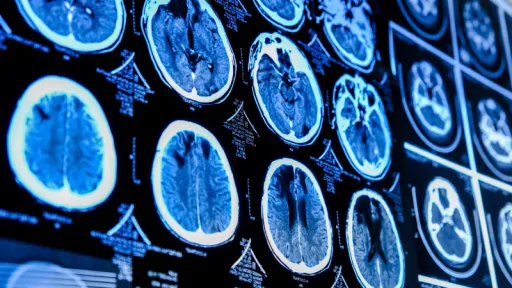

Un cercetător important din Canada susține că nu i s-a permis să investigheze o boală neurologică misterioasă care afectează populația provinciei New Brunswick și se teme că simptomele inexplicabile ale celor peste 200 de pacienți se vor agrava, potrivit The Guardian și digi24ro.

Oficialii sanitari din New Brunswick au avertizat în 2021 că peste 40 de localnici suferă de un sindrom posibil necunoscut, cu simptome similare cu cele ale bolii degenerative Creutzfeldt-Jakob.

Simptomele sunt variate și dramatice: unor pacienți a început să le curgă saliva din gură, în timp ce alții se simțeau de parcă aveau gândaci care li se plimbau pe piele.

„O expunere la factori de mediu - sau o combinație de expuneri - a declanșat sau a accelerat o serie de sindrome neurodegenerative” în cazul oamenilor aparent susceptibili la diferite tulburări proteopatice (proteine cu structuri anormale), potrivit lui Coulthart, care este un cercetător cu mare experiență aflat la conducerea Sistemului de Supraveghere a Bolii Creutzfeldt-Jakob din Canada.